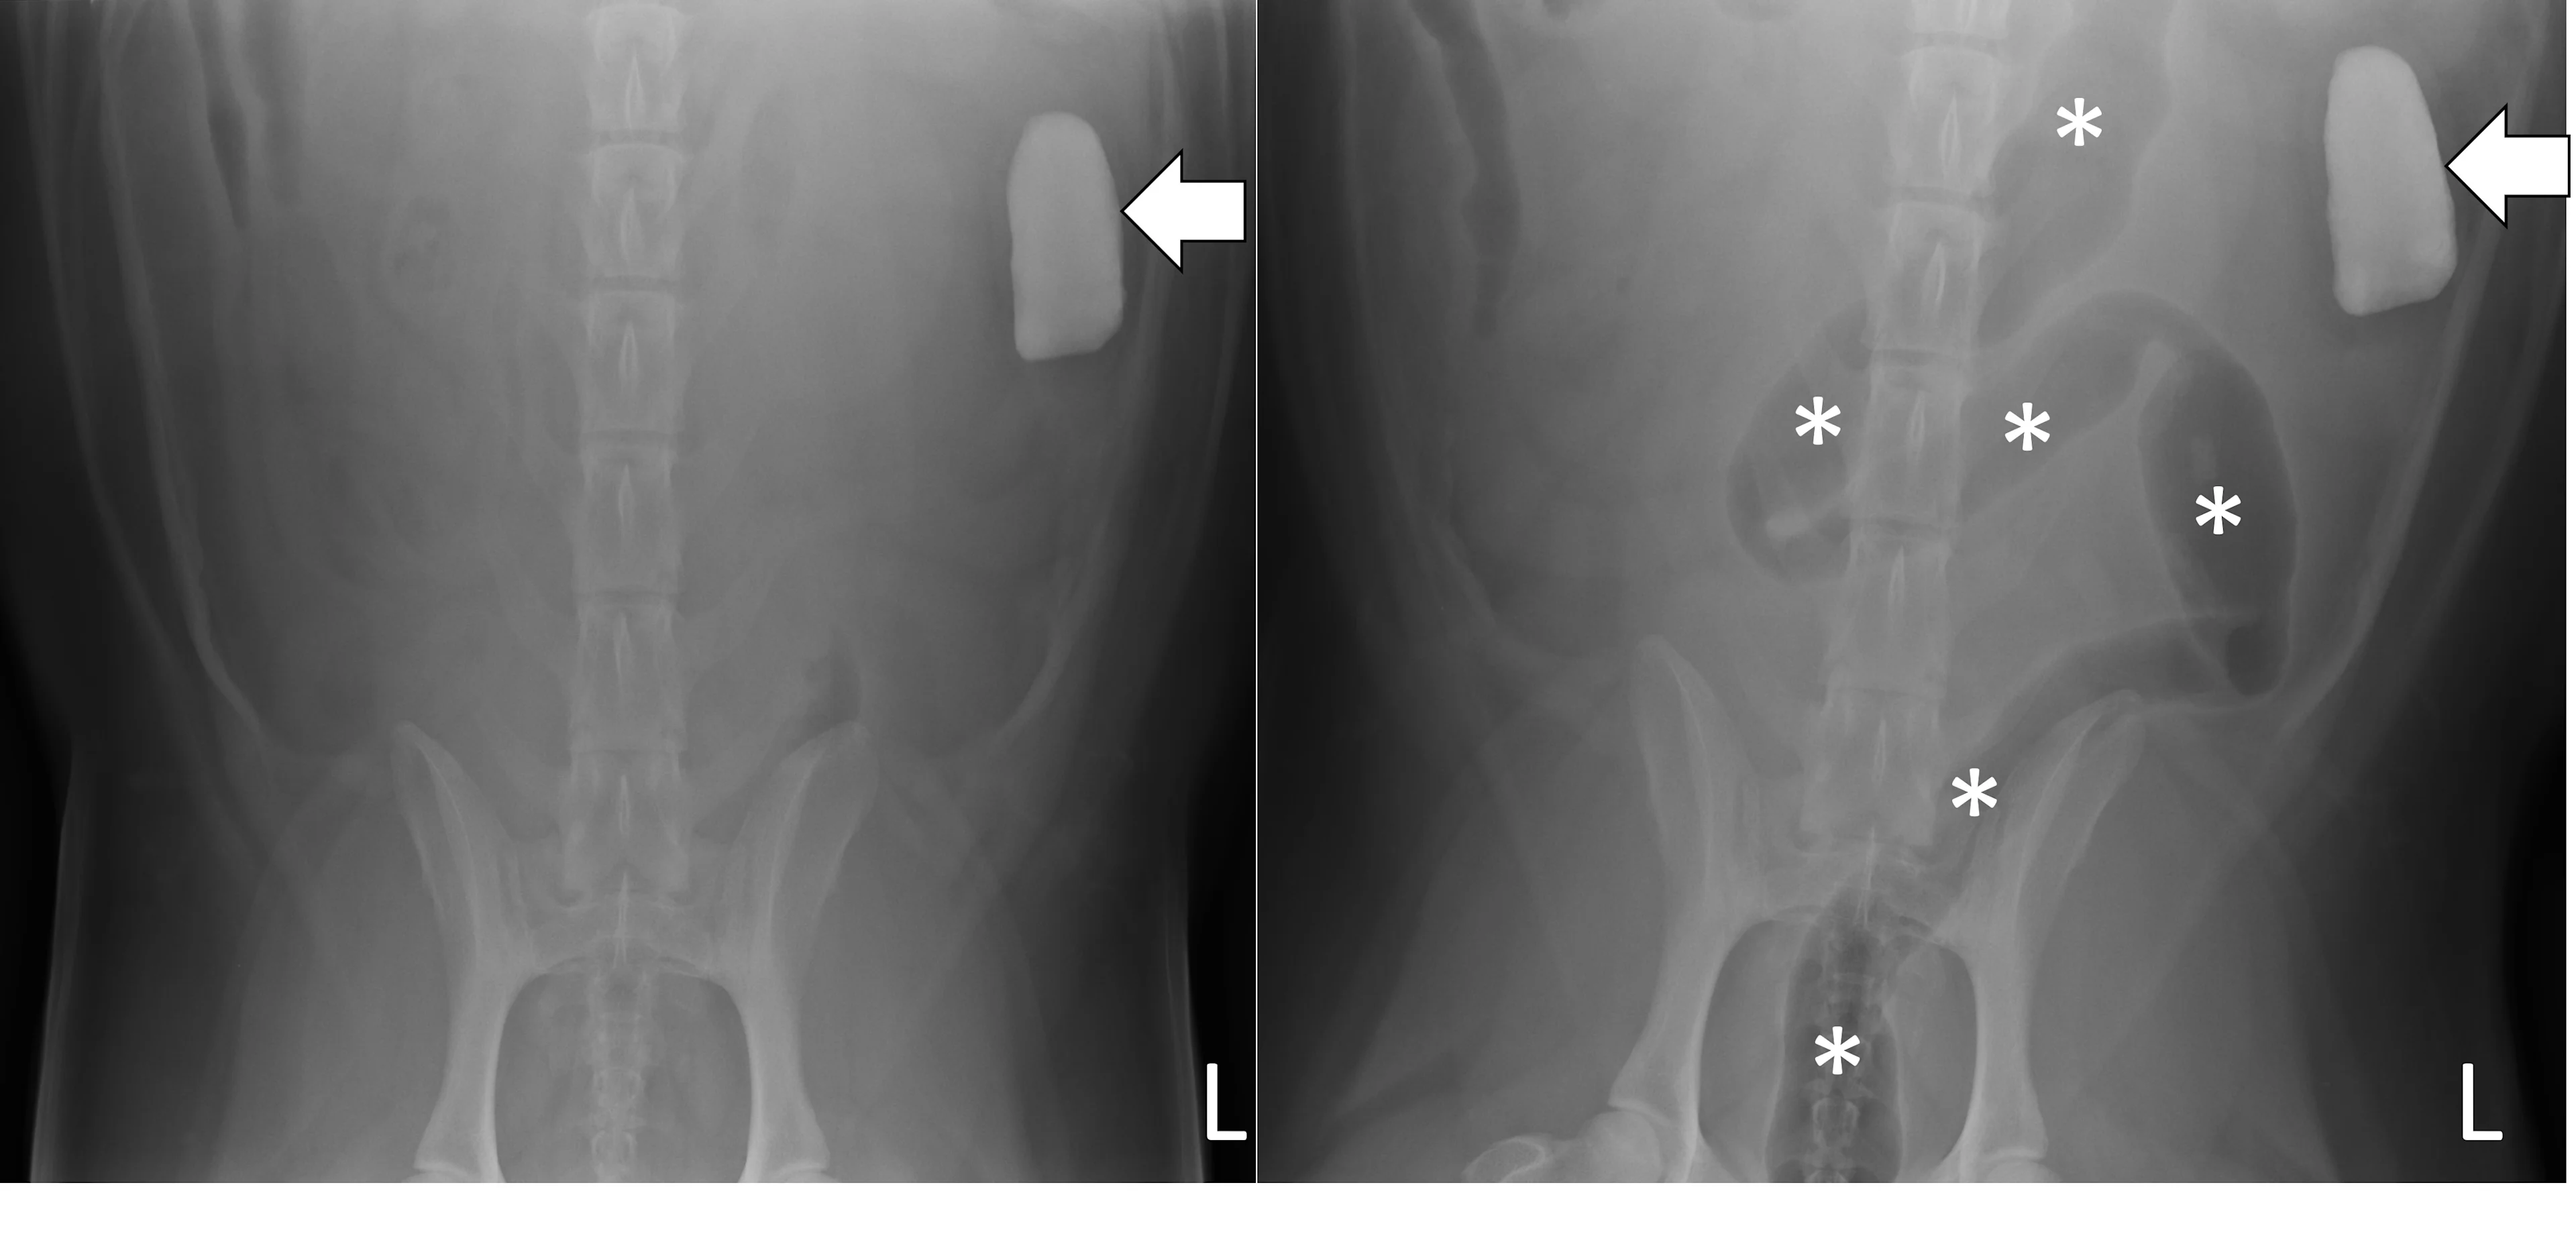

A complete radiographic study includes left lateral, ventrodorsal, and right lateral projections. Obtaining a left lateral projection and performing projections in the aforementioned order can improve visualization of the pylorus and duodenum by shifting gas into the lumens.3 Normal intraluminal gas is an in vivo negative contrast agent that can make soft tissue opaque foreign bodies (eg, cloth) easier to see (Figure 1).

Three-view abdominal radiographs of a 6-year-old spayed dachshund with an acute pyloric outflow obstruction secondary to a surgically confirmed foreign body (cloth). The stomach (pound signs) is moderately dilated with gas and fluid. On the left lateral and ventrodorsal projections, gas outlines an irregularly shaped soft tissue opaque foreign body (arrows) within the pylorus that extends into the duodenum. On the right lateral projection, the foreign body is more difficult to see because it is surrounded by similarly opaque gastric fluid.